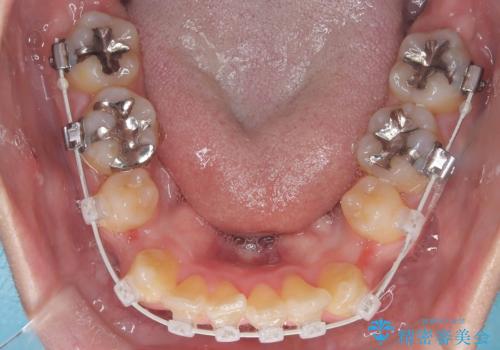

- 「歯のデコボコと前歯が引っ込んでいるのを治したい」を主訴に来院された患者様です。

デコボコの量が多かったため上下左右4を抜歯してワイヤー矯正で治療を行いました。

正面から見たときに右上2が全く見えないくらい、右上2が後ろに引っ込んでいる状態でしたが綺麗に並べる事が出来ました。

スムーズに治療を進める事ができ、2年2か月で治療をお終えました。